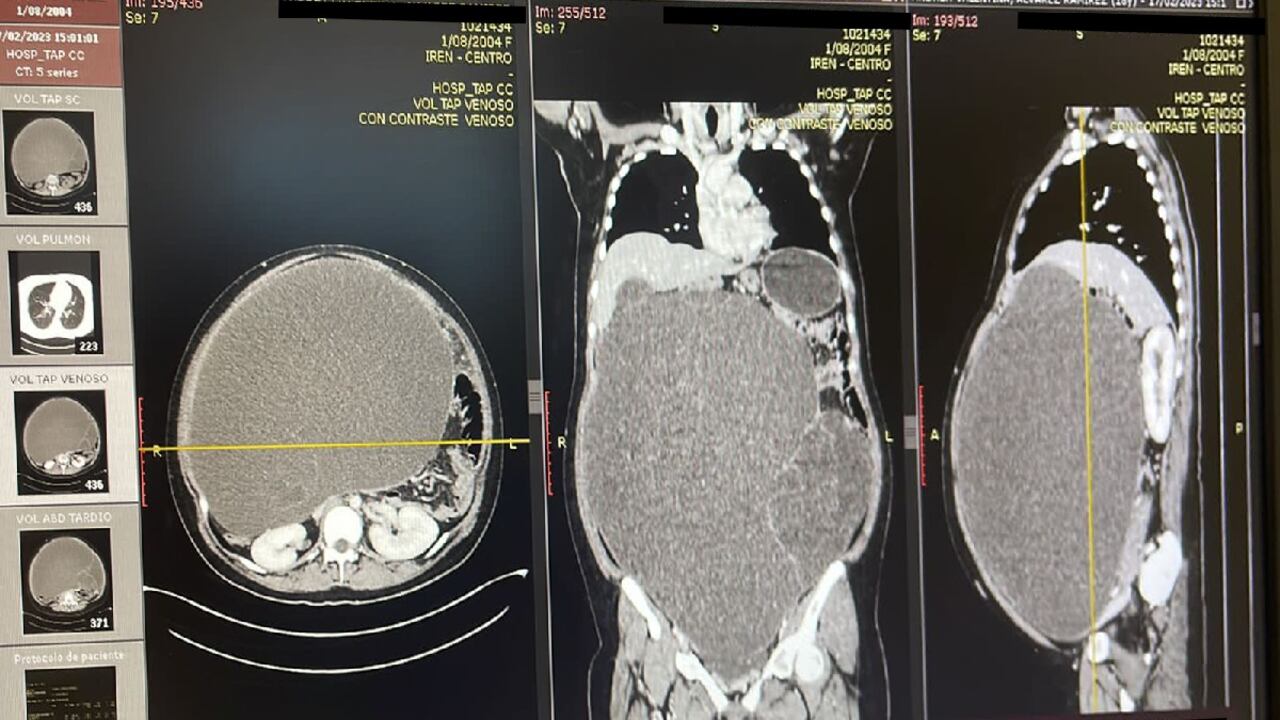

Despues de los exámenes pertinentes, los médicos se dieron cuenta que la gran masa que estaba en esta zona de su cuerpo venía de sus ovarios y estaba convirtiéndose en un problema de 12 kilos que le causaba todo tipo de dolencias al punto de poner su propia vida en riesgo.

Se necesitaron 10 horas para que a la mujer le pudieran extraer esta inmensa masa que pesaba más de 10 kilos y que ella venia cargando en su cuerpo. El nombre científico de esta afección es cistoadenoma seroso de ovario. Al pesarlo y ver su gramaje, quedaron asombrados y se convirtió en el mas pesado que se ha sacado en el centro médico donde fue atendida. La mujer ya se encuentra fuera de peligro y se encuentra recuperándose satisfactoriamente.